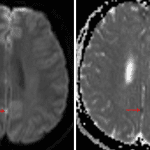

- FLAIR signal hyperintensity in a right occipital sulcus and possible adjacent cortical FLAIR signal hyperintensity without definite corresponding restricted diffusion or enhancement (possibly representing leptomeningeal spread)

- Small focus of restricted diffusion along the interhemispheric fissure without definite corresponding enhancement (also possibly a leptomeningeal tumor deposit)